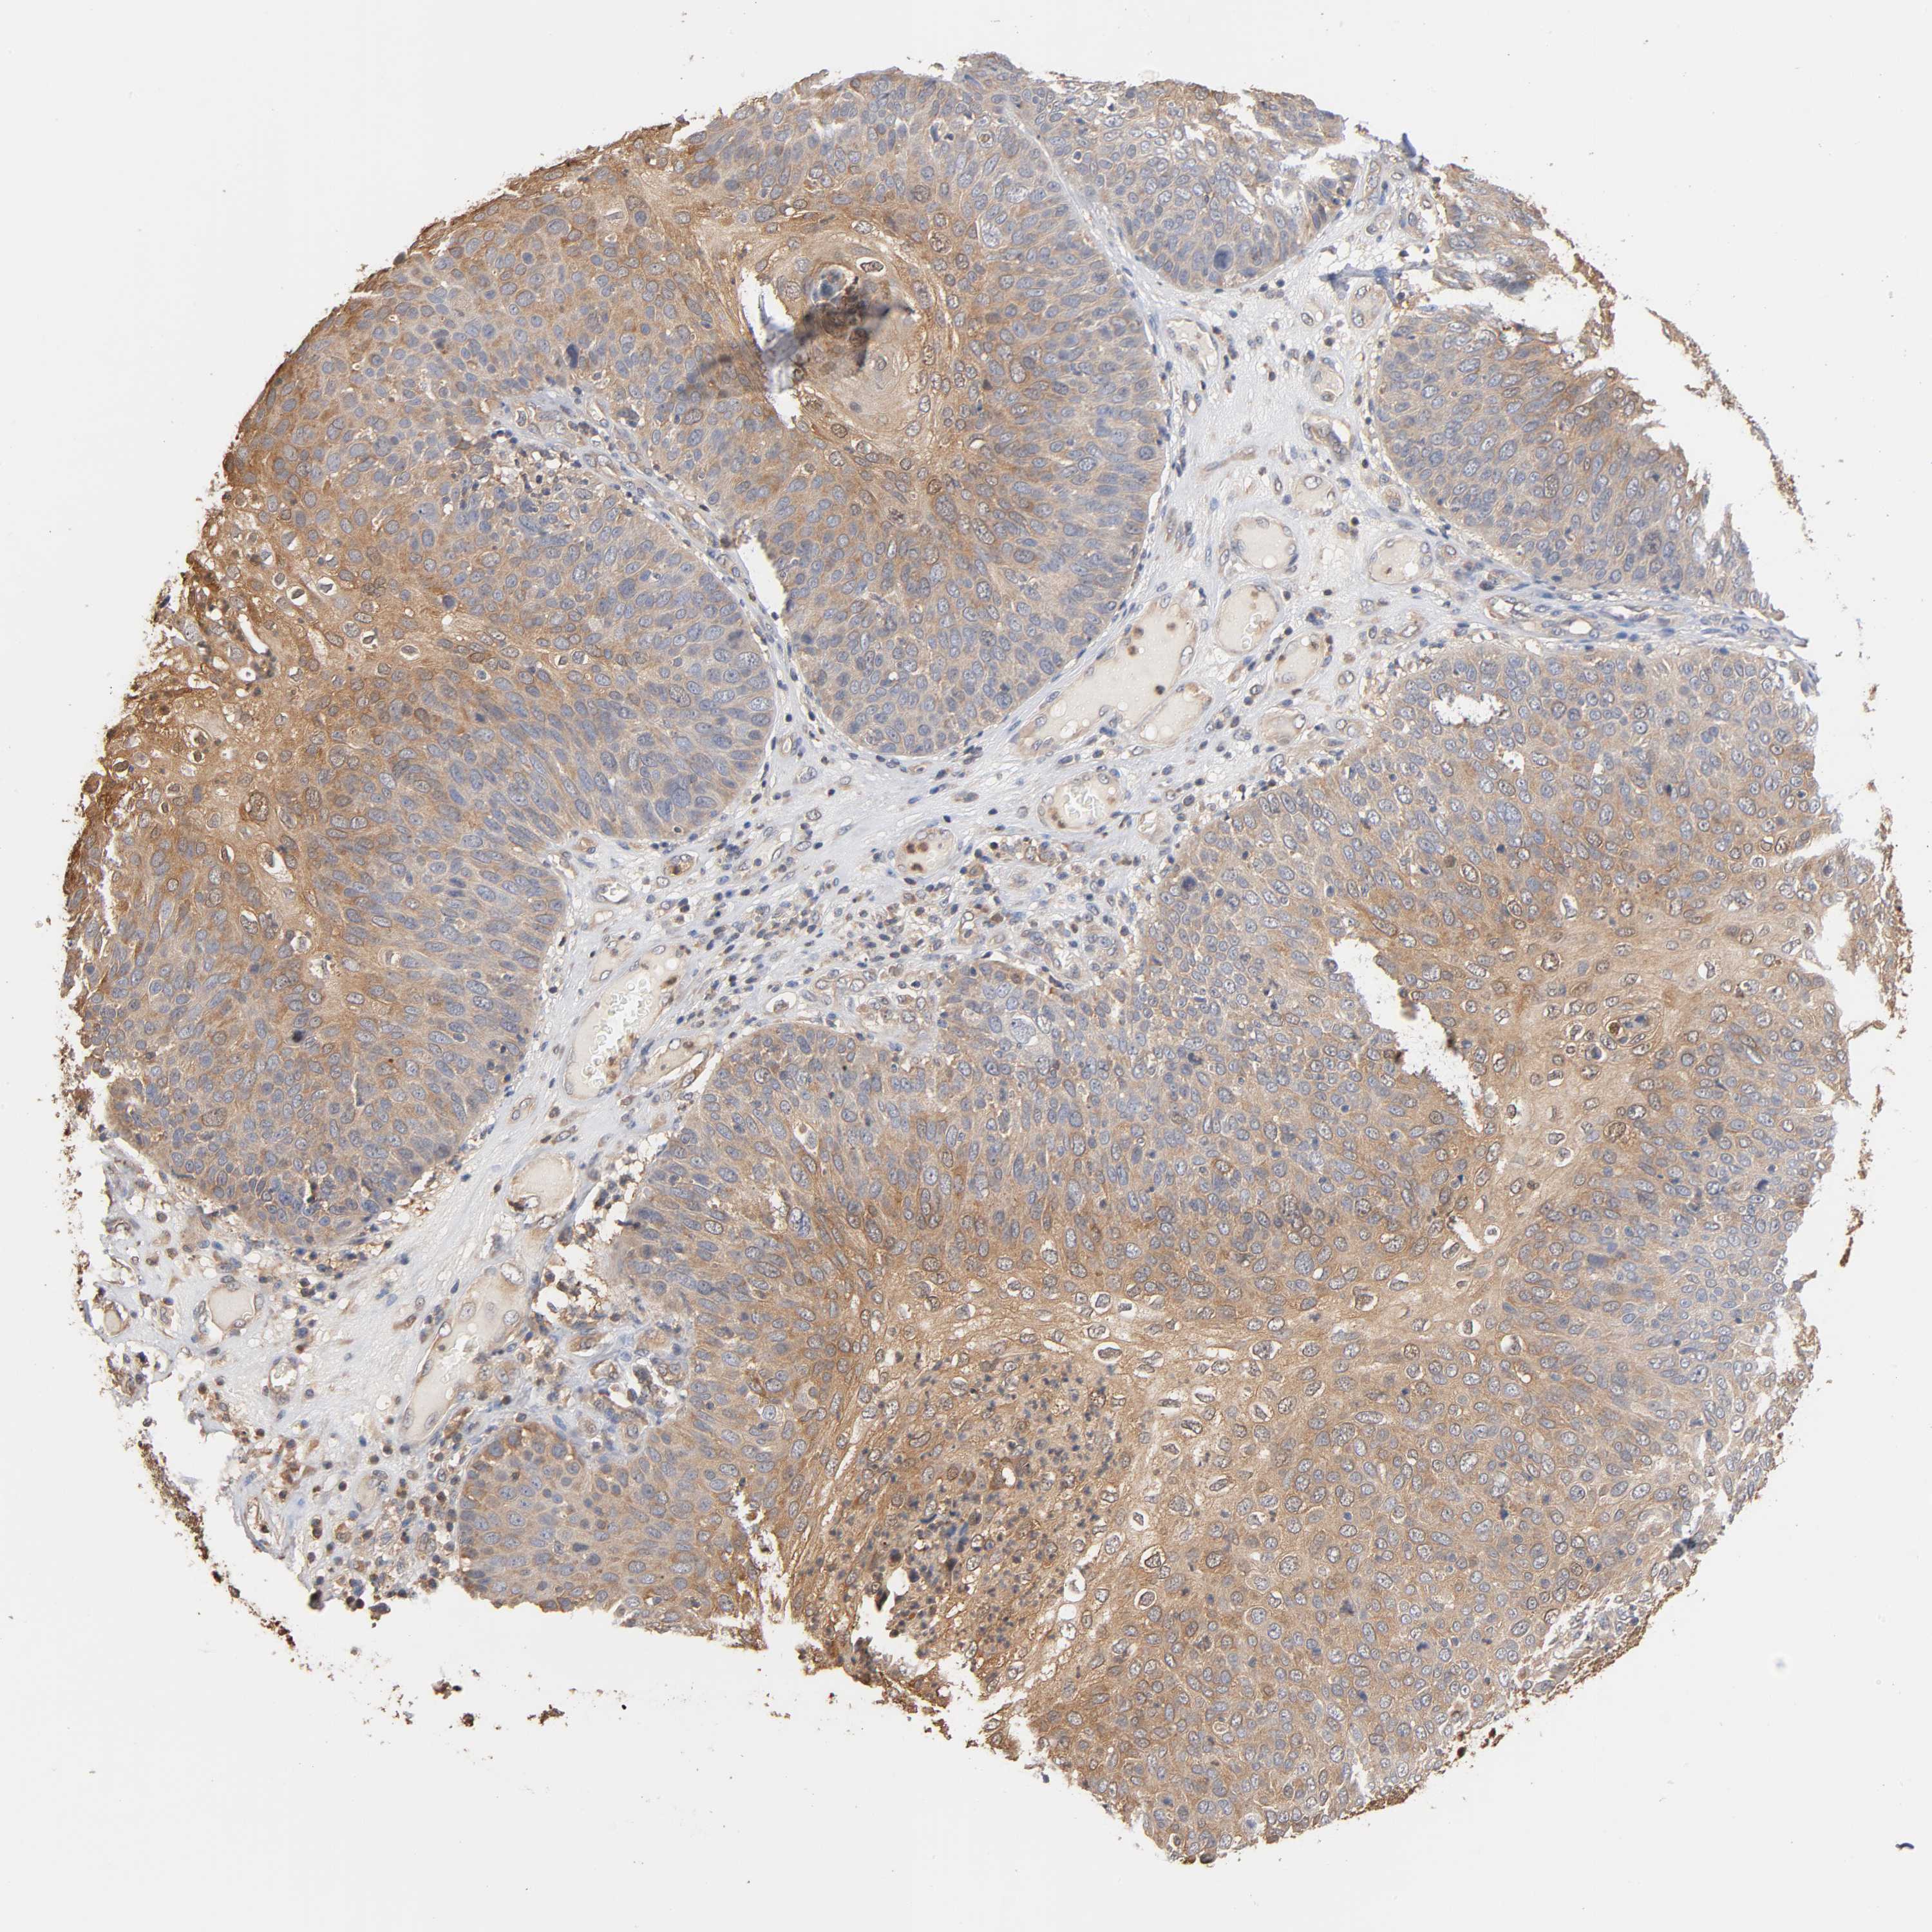

SKIN CANCER - Protein expressioni

A mouse-over function shows sample information and annotation data. Click on an image to view it in a full screen mode. Samples can be filtered based on level of antibody staining by selecting one or several of the following categories: high, medium, low and not detected. The assay and annotation is described here.

Each image is clickable and will lead to virtual microscopy that enables deeper exploration of all samples and also displays staining intensity scores, fraction scores and subcellular localization as well as patient and tissue information for each sample.

Antibody HPA004177

Staining

High

Medium

Low

Not detected

Intensity

Strong

Moderate

Weak

Negative

Quantity

>75%

75%-25%

<25%

None

Location

Nuclear

Cytoplasmic/membranous

Cytoplasmic/membranous,nuclear

Squamous cell carcinoma, NOS